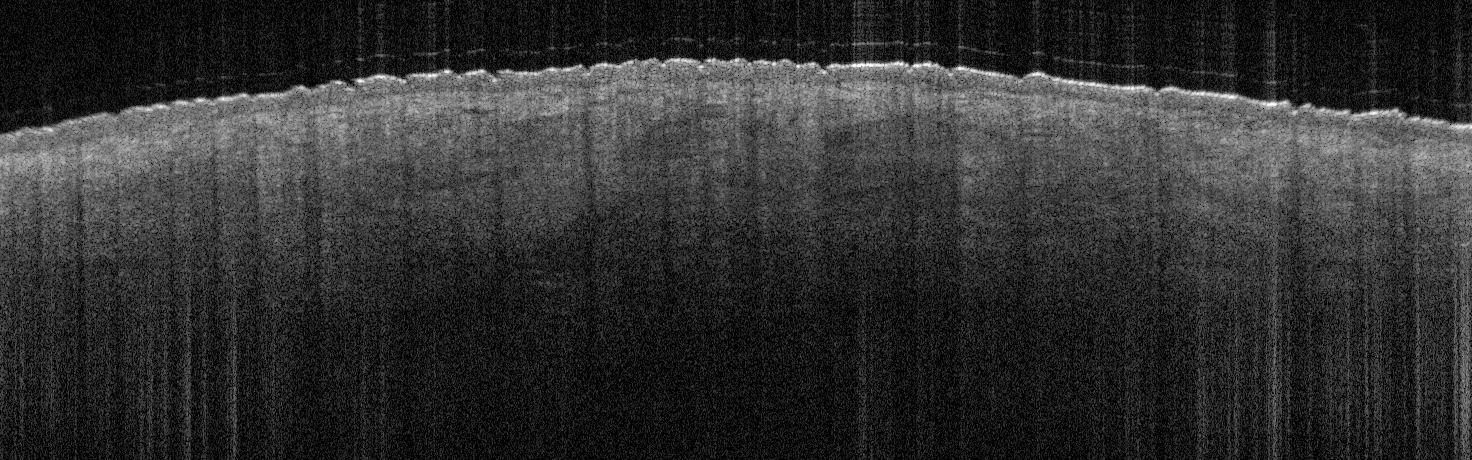

VA34: Right Temple, Actinic Keratosis, Hypotrophic, Focally reaching the base.

- White arrow denotes hair follicle

VA34: Right Temple, Adjacent, Normal

- Note normal hair follicle presentation